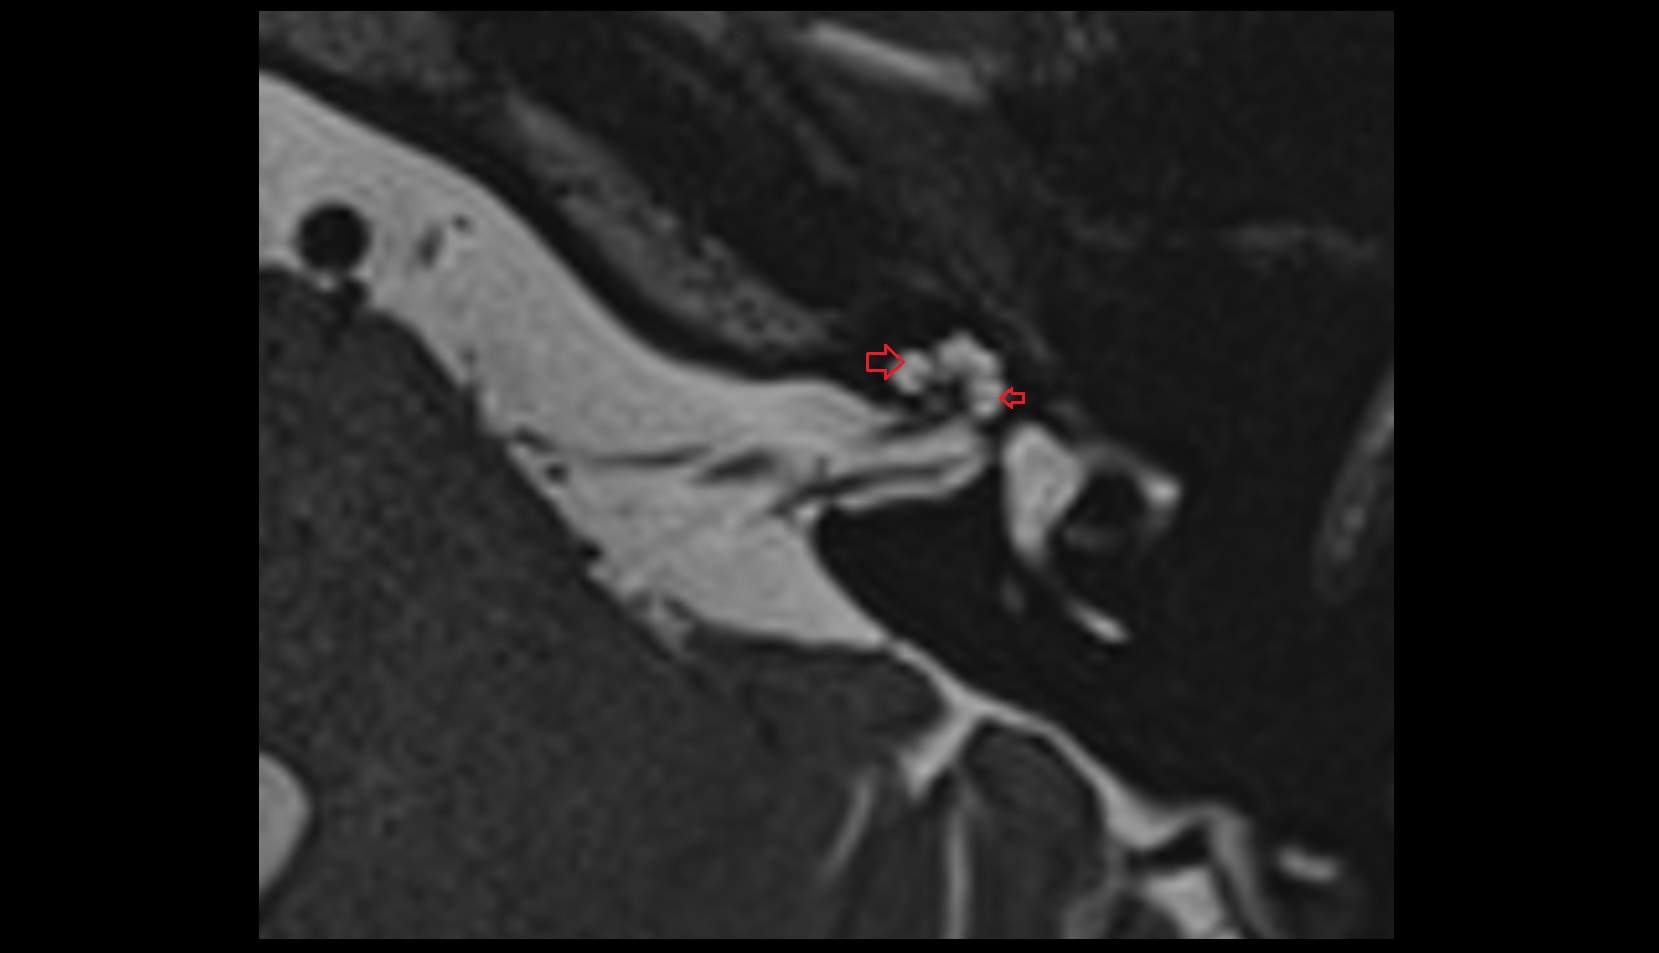

- Temporomandibular joint

- Articular disc of temporomandibular joint

- Articular eminence

- Mandibular condyle

- Mandibular fossa